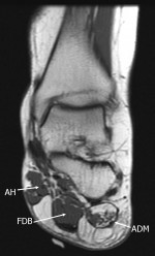

In this report, bilateral Baxter's neuropathy developed in a 42-year-old woman secondarily to bilateral plantar fasciitis. On MR images, fatty atrophy of the abductor digiti minimi muscles was found in both feet, revealing high-signal areas in the T1-weighted images and low-signal areas in the T2-weighted images. Additionally, findings of plantar fasciitis were observed in both feet.

To the authors' knowledge, no case of bilateral Baxter's neuropathy secondarily to plantar fasciitis has been reported. Baxter's neuropathy and causative disorders are easily recognized with help of typical MRI findings. Selective fatty atrophy of the abductor digiti minimi muscle is the unique sign of this neuropathy. Recognition of unique MRI findings of this rare condition that can cause heel pain are important since they provide an effective treatment plan.